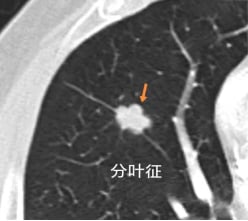

分叶征:恶性结节的生长印记

分叶征是指肺结节边缘呈现出不规则的、凹凸不平的分叶状轮廓,如同被雕刻的树叶。这种形态的形成,源于肿瘤内部生长速度的不均衡以及周围组织对肿瘤扩张的限制。根据分叶的深度,可细分为深分叶、中分叶和浅分叶。通常,弦弧距与弦长之比大于等于0.4为深分叶,小于等于0.2为浅分叶,介于0.2至0.4之间为中分叶。在恶性肺结节中,深分叶征的出现频率更高,是提示肺癌可能性的重要影像学标志。